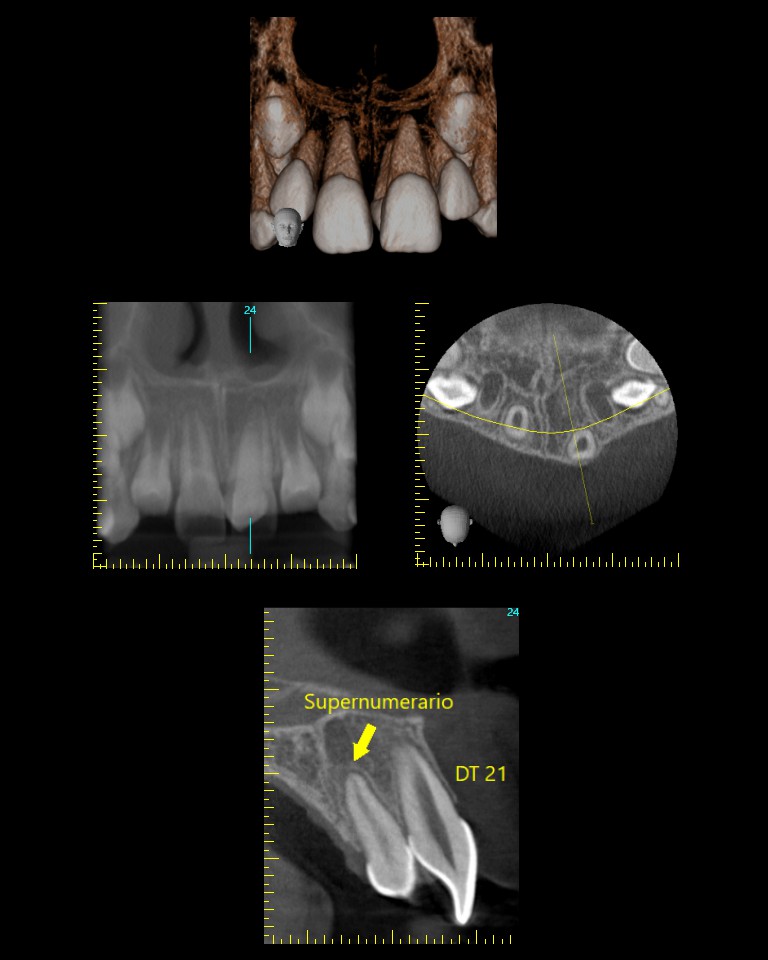

- CBCT: La tomografía computarizada de haz cónico es una imagen en 3D que proporciona imágenes de alta resolución del complejo craneofacial. Permite evaluar la cantidad y calidad ósea para la colocación de implantes dentales, adicionalmente es útil para la evaluación de dientes incluidos, fracturas y reabsorciones radiculares, entre otros.

La tomografía computarizada de haz cónico (CBCT) proporciona imágenes en 3D de alta resolución del craneofacial, ideal para planificar implantes, evaluar dientes incluidos, fracturas y reabsorciones radiculares.